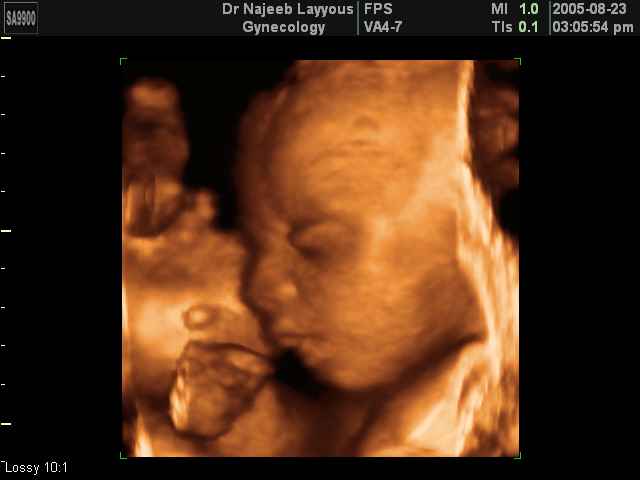

- 3D Fetal Profile Ultrasound Scan Photos

3D Fetal Profile Ultrasound Scan Photos | Dr N Layyous